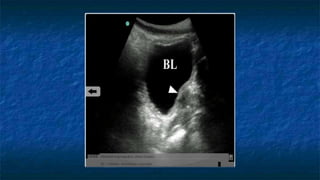

FAST: Pelvis exam

 Pelvis: Transverse Axis

 Normal Anatomy

 Evaluating Bladder

 Well cirucumscribed

 Contains fluid that

appears anechoic

FAST: Pelvis exam - Pathology

Transverse

Bladder

FF